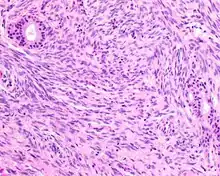

- Infiltrative, highly cellular spindled cell neoplasm is poorly circumscribed and unencapsulated. Bone destruction or invasion is common. The cells show medium to long fascicles (nerve fibers), with a herringbone pattern. The cells are remarkably uniform with elongated nuclei. Delicate strands of intercellular collagen without ropy or dense deposition are seen. A very characteristic concurrent surface-type respiratory epithelial proliferation is found from the surface or in small cystic spaces around the cancer cells, often forming glands. The background may have a rich vascularity and usually has a small number of scattered lymphocytes. Extra growths or mitoses are rare, while necrosis, ulceration, and hemorrhage are usually absent.

- Fibrosarcoma can be very similar, although nerve fibers and the herringbone pattern tend to be longer and more well developed.

- Synovial sarcoma is almost histologically identical, but genetic translocation (SS18-SSX1 or SSX2) is shown through fluorescence in situ hybridization or RT-PCR.

- Malignant peripheral nerve sheath tumor, such as triton tumor, has distinctive alternating light and dark cellular areas, an association with peripheral nerves, and usually a high-grade tumor with pleomorphism, necrosis, and increased mitoses. Generally, it shows reactivity with S100 protein and SOX10, while negative for SMA or MSA.

- Leiomyosarcoma has fascicular (nerve tract) architecture, with cigar-shaped nuclei showing blunt ends, perinuclear halos (cellular nuclear shrinking), and eosinophilic cytoplasm. Much stronger reactivity occurs with desmin and SMA, while it is usually negative with S100 protein.